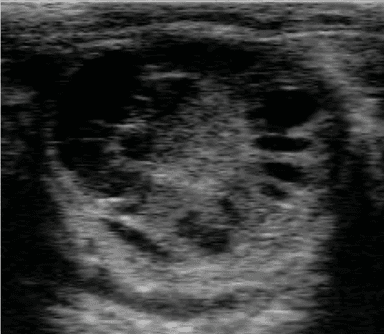

Итак, сегодня предлагаю к обсуждению такую проблему как кистозная дегенерация фолликулов яичника, в простонародье - кисты.

По обычной классификации мы знаем, что есть фолликулярные кисты и лютеиновые кисты (кисты 1 типа и 2 типа).

Предлагаю рассмотреть снимки и в комментариях ответить, какие кисты вы видите и кисты ли это, а потом будем разбираться с каждым случаем в отдельности!